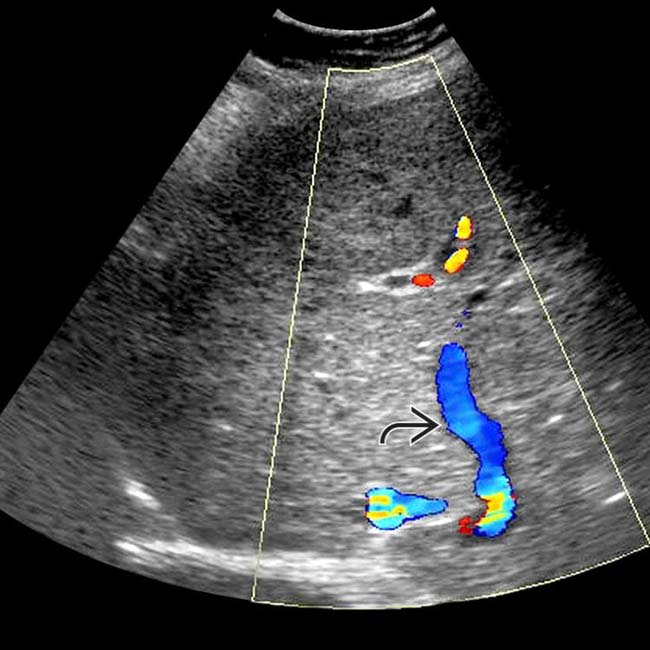

Hepatofugal flow